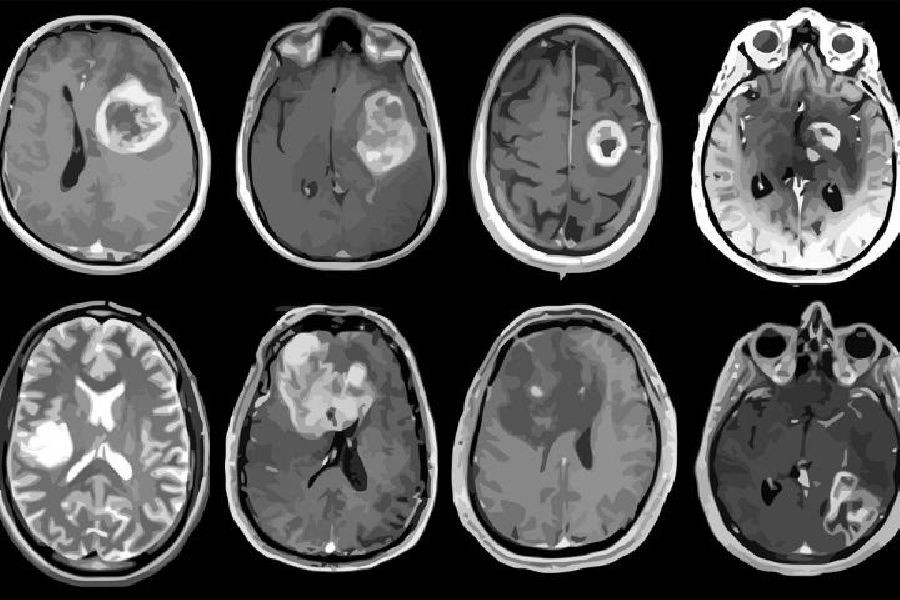

Un ensayo clínico inicial en personas con el cáncer cerebral mortal, el glioblastoma, ha demostrado que un fármaco experimental de ácido nucleico esférico (ANE) desarrollado por científicos de la Universidad Northwestern, en Estados Unidos, pudo atravesar la barrera hematoencefálica y provocar la muerte de células tumorales.

El estudio de fase 0 se realizó con ocho personas que tenían glioblastoma recurrente en el Centro Integral de Cáncer Robert H. Lurie de la Universidad Northwestern. En la fase 0, los investigadores usan una pequeña dosis de medicamento para asegurarse de que no sea dañino para los humanos antes de comenzar a usarlo en dosis más altas en ensayos clínicos más grandes.

Los participantes del estudio recibieron el fármaco por vía intravenosa antes de la cirugía. Después de la extirpación del tumor, Kumthekar y su equipo estudiaron los tumores para determinar qué tan bien el fármaco atravesaba la barrera hematoencefálica y su efecto sobre las células tumorales.